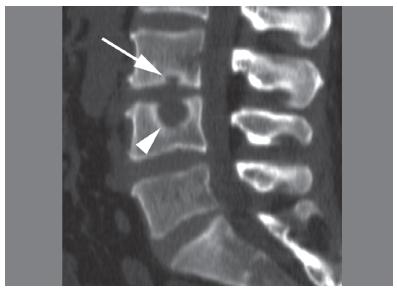

Изображение: Marcello Henrique Nogueira-Barbosa, Michel Daoud Crema, Carlos Fernando Pereira da Silva Herrero, Wagner Pasqualini, Helton Luiz Aparecido Defino, CC BY 4.0, via Wikimedia Commons

Диагноза

Диагностицирането на телцата на Шморл се извършва чрез снемане на анамнеза, физикален преглед и чрез образни изследвания на гръбначния стълб, които обикновено изобразяват областта на долната част на гърба. Може да се приложат:

Обикновено чрез образните методи се установява дефект в крайната пластинка и херниирал дисков материал в тялото на прешлена